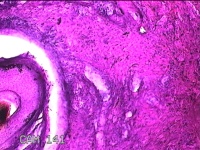

会阴部结节

性别

男

年龄

34岁

临床诊断

会阴部良性肿瘤

一般病史

发现会阴部结节1周。

标本名称

大体所见

灰白粉红色组织1.3x1.2x0.3cm一块,表面光滑,切面灰白粉红色。质软。